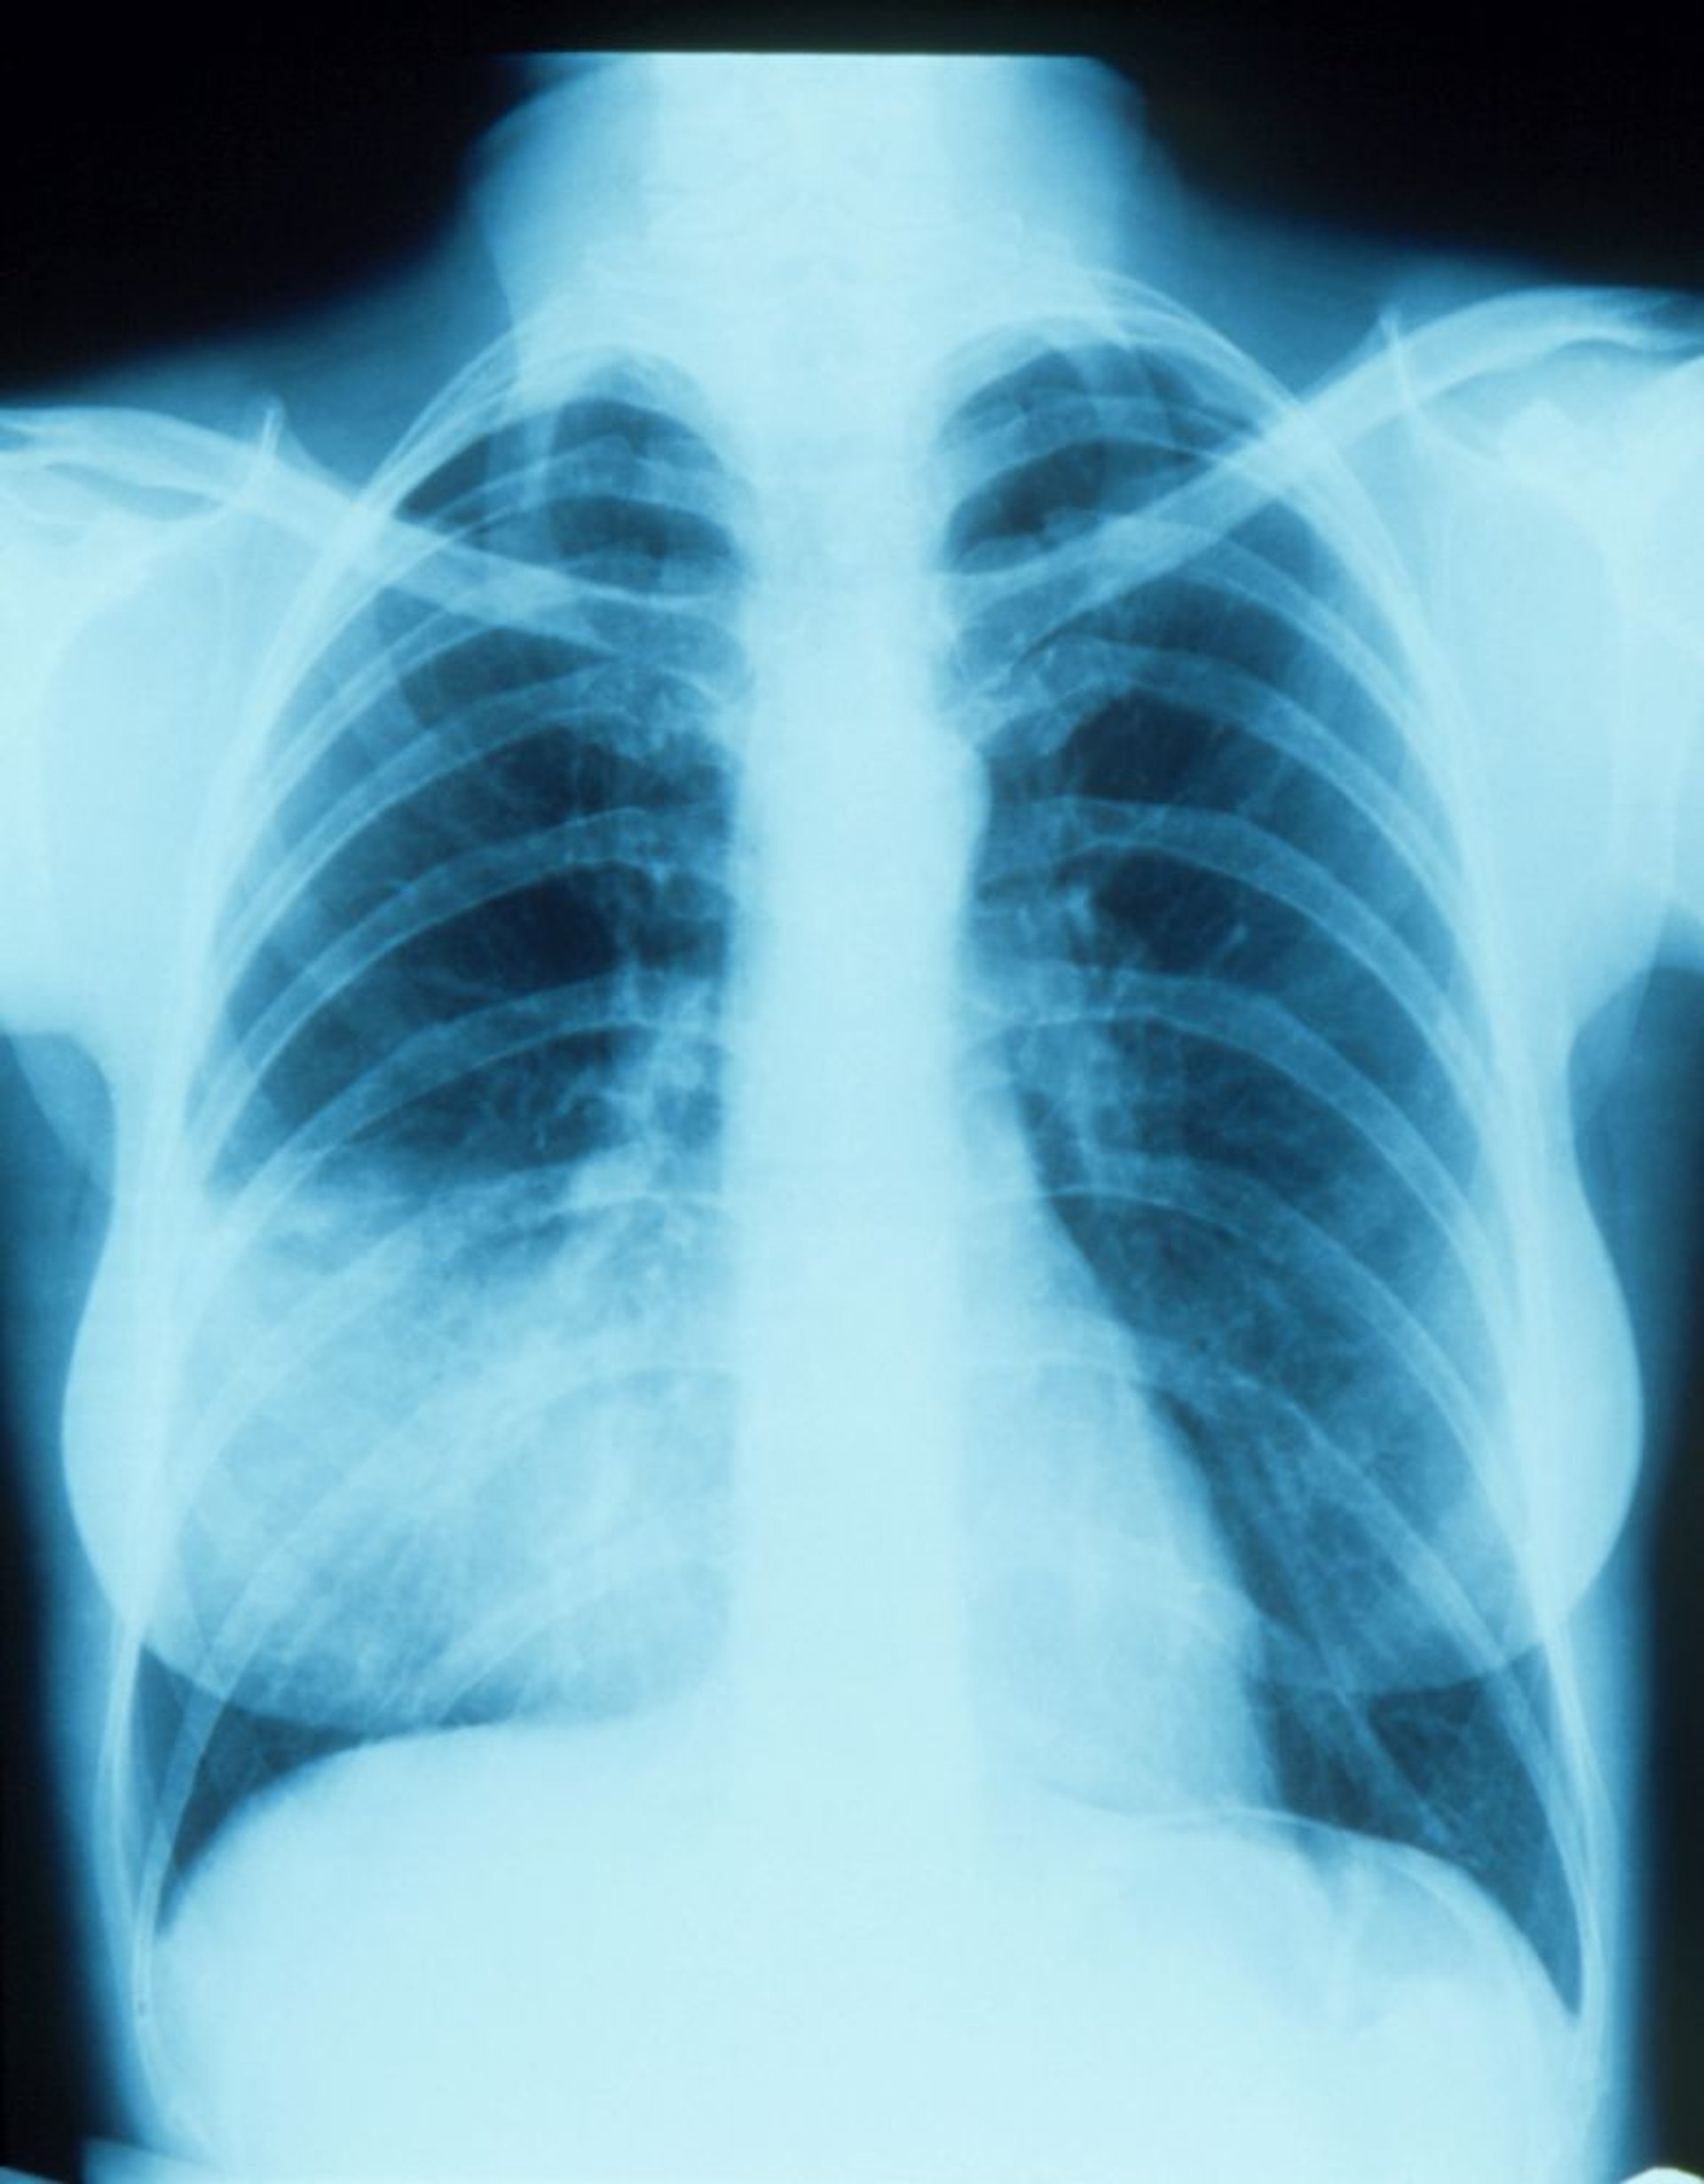

Viêm phổi thùy giữa bên phải kèm theo dấu hiệu xóa bờ

Phim chụp X-quang phổi này cho thấy một chỗ thâm nhiễm dường như hòa trộn với viền tim bên phải (dấu hiệu xóa bờ). Dấu hiệu xóa bờ cho biết vị trí liền kề của 2 cấu trúc có mật độ bức xạ tương tự nhau; phần phổi tiếp giáp với bờ tim phải là thùy giữa bên phải, vì vậy đó là phần có thâm nhiễm và viêm phổi.